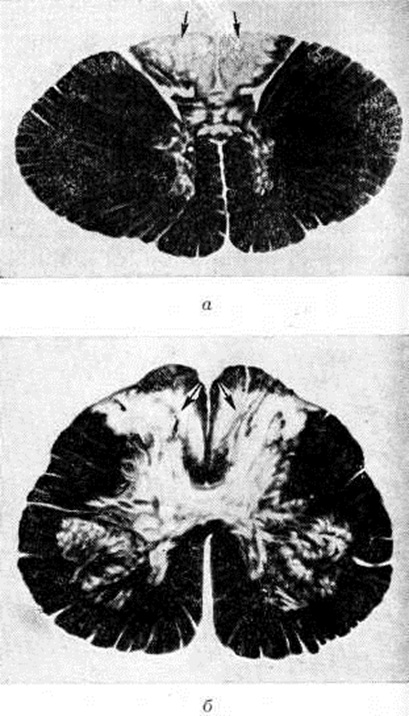

Рис. 2.

Рентгенограммы коленного сустава (а), проксимальной части бедра и тазобедренного сустава (б), поясничного отдела позвоночника (в) при спинной сухотке: а — деструкция внутреннего мыщелка большеберцовой кости (указана стрелкой); б — массивная костная мозоль, образовавшаяся после патологического перелома проксимальной части диафиза бедренной кости (указана стрелками); в — тело IV поясничного позвонка сплющено, на уровне II—IV поясничных позвонков костные разрастания (указаны стрелками).

К основным рентгенологическое признакам табетических артропатий относят патологический внутрисуставные переломы (смотри полный свод знаний), которые обычно бывают многооскольчатыми. Иногда патологический переломам сопутствует массивный некроз суставных концов костей (рисунок 2, а). Распад костной ткани в суставных концах костей приводит к их взаимному смещению — к подвывиху и вывиху. Отторгнутые в результате патологический внутрисуставного перелома костные фрагменты нередко выявляются рентгенологически как внутрисуставные свободные тела. В результате длительного функционирования поражённого сустава в патологический условиях в нем может произойти своеобразная взаимная отшлифовка суставных поверхностей. При менее выраженной деструкции костной ткани выявляется лишь уплощение естественного рельефа суставных поверхностей костей.

Важное значение в диагностике табетической артропатии (смотри полный свод знаний) имеют отсутствие костного анкилоза (смотри полный свод знаний), патологический обызвествления и окостенения в суставной капсуле и в околосуставных тканях. Этот процесс метапластического костеобразования рентгенологически проявляется бесформенными «известковыми» тенями вокруг деформированного сустава. В метафизах трубчатой кости при значительном разрушении суставных её концов могут быть выявлены периостальные наложения. При Спинная сухотка, несмотря на значительные деструктивные изменения в костях, остеопороз (смотри полный свод знаний) обычно отсутствует; часто наблюдают выраженный остеосклероз (смотри полный свод знаний). Внесуставные патологический переломы при Спинная сухотка сопровождаются продуктивной реакцией с образованием большой костной мозоли (рисунок 2, б), причём эта реакция более выражена в диафизах трубчатых костей и при значительном смещении отломков. В некоторых случаях патологический перелом может не сопровождаться заметной периостальной реакцией. Преобладанием продуктивных изменений отличаются и поражения позвоночника (спондилопатии) при Спинная сухотка (рисунок 2, в).